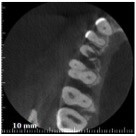

Come potrai vedere in questo video, il mio pensiero non faceva una piega. Con microsopio e cone beam operare casi del genere è una cosa è perfettamente fattibile e, ti dirò, non è nemmeno difficile.

Visto?

E tu credi che questo dente durerà meno di 3 anni? A meno che non ci sia un cataclisma in questi due mesi, ti posso già anticipare di no, perché a novembre questa cura compirà tre annetti e il dente è perfetto sia clinicamente che radiograficamente.